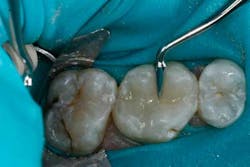

An example of an ideal case for which bulk filled composite (i.e., Tetric EvoCeram® Bulk Fill) is indicated is a 43-year-old female who presented with a defective amalgam restoration on the occlusal of tooth No. 14 (Figs. 1 and 2). The treatment plan involved removing the defective amalgam restoration, any secondary caries, and restoring the tooth with a direct bulk-fill composite (i.e., Tetric EvoCeram® Bulk Fill).

The tooth was prepared and a total etch technique utilizing 37% phosphoric acid was performed (Figs. 3 through 5). After the etchant was rinsed, a desensitizer was placed and blotted to leave a moist dentin surface for bonding (Fig. 6). The bonding agent was applied; the ethanol solvent was air evaporated using a warm air dryer; and the adhesive light-cured for 10 seconds (Figs. 7 and 8).